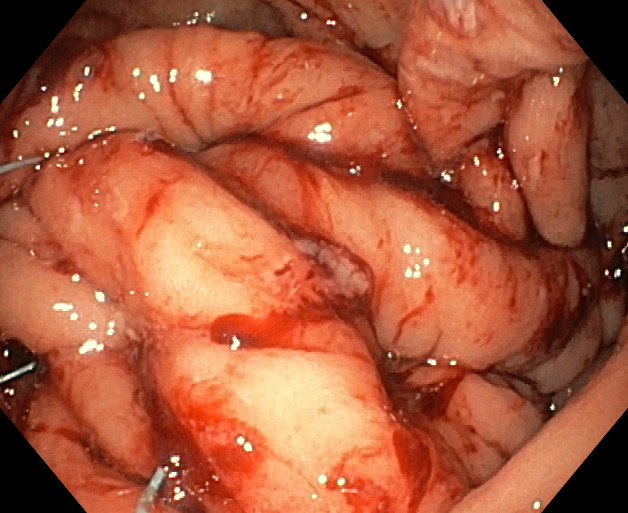

APOLLO

Comúnmente conocido como “manga gástrica endoscópica” o “manga gástrica sin cirugía”, el método Apollo es una técnica endoscópica mínimamente invasiva que permite reducir el estómago entre un 60 y un 80% de su tamaño inicial, sin realización de incisiones externas y, por tanto, sin cicatrices. Está indicada para pacientes con un IMC entre 30 y 40, o para pacientes con un IMC superior a 40 que no desean enfrentarse a técnicas quirúrgicas para reducción de peso de mayor envergadura y por ende, de mayor riesgo.

Mediante un sistema de sutura acoplado a un endoscopio, se sutura el estómago “desde dentro” dándole un aspecto similar al conseguido por la cirugía de gastrectomía vertical laparoscópica (manga gástrica quirúrgica), pero con menor riesgo quirúrgico y muy buenos resultados a medio y largo plazo. De esta manera se limita la cantidad de comida que puede entrar en el estómago e igualmente hace que la digestión sea más lenta, favoreciendo enormemente la saciedad y la pérdida de peso. Es una técnica definitiva, pero por vía oral, ni realizar heridas abdominales ni cicatrices.

Los pacientes, tras la intervención, permanecen ingresados en hospitalización por lo general no más de 16-24 horas, ya que se trata de una intervención mínimamente invasiva y de bajo riesgo, por lo que la tolerancia suele ser excelente. La incorporación a su vida cotidiana es rápida, en 2-3 días por lo general. El postoperatorio es muy bueno en general, con dolor o molestias abdominales controlables con medicación y que no suelen ir más allá de los 2-3 primeros días. A los pocos días de la operación se realiza un control médico para comprobar que el paciente evoluciona de forma correcta y, a partir de ahí, se comienza el programa de seguimiento.

Los pacientes sometidos a la técnica pierden peso de una manera muy fisiológica y progresiva desde el mismo momento de la intervención. Además, tras la intervención el paciente comenzará un programa de reeducación alimentaria y un seguimiento médico, nutricional y psicológico para adquirir unos hábitos saludables y que le permitan mantener el peso a largo plazo. El programa de seguimiento lo establecemos en 18 meses, con visitas regladas pero abiertas a las necesidades del paciente.